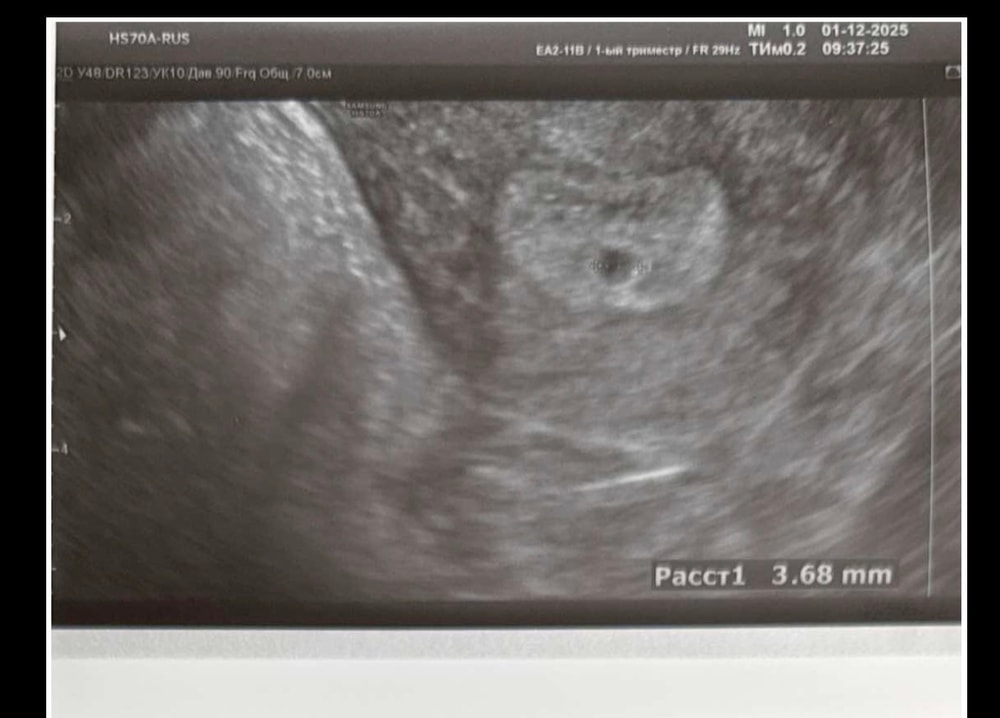

ЭКО 40+. Второй протокол. 18ДПП первое узи.

Моя ЭКО-история (от начала пути до родов)Вот мы и докатились до первого узи. Перенос был 13.11, две четырехдневки (с дс). Акушерский срок сегодня 5 нед. 1 д.

Сдавала ХГЧ три раза на 9, 11 и 13 дпп (62,168,514 ед.). На сегодня узи назначила моя репродуктолог. Но смотрела не она, а поликлиника, в которой я обслуживаюсь.

Напоследок пару свежих фоточек😎